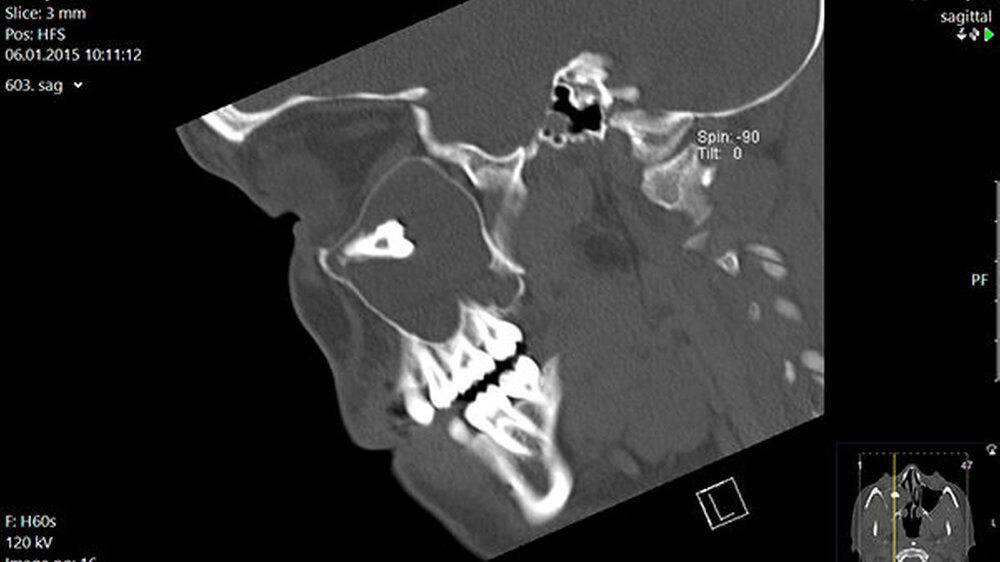

In der regionalen Klinik (Winterberg-Krankenhaus Saarbrücken) wurde zusätzlich eine kontrastmittelunterstützte Computertomografie der Nasennebenhöhlen durchgeführt (Abbildungen 2 und 3), die den Befund bestätigte und präzisierte.

Intraoperativ entleerte sich reichlich eingedicktes Sekret. Die dort ebenfalls veranlasste postoperative Histologie ergab die Kombination einer Kieferhöhlenzyste (respiratorisches Epithel) mit einer odontogenen Zyste (mehrschichtiges nicht keratinisiertes Plattenepithel). Der weitere Verlauf war erfreulicherweise unkompliziert.